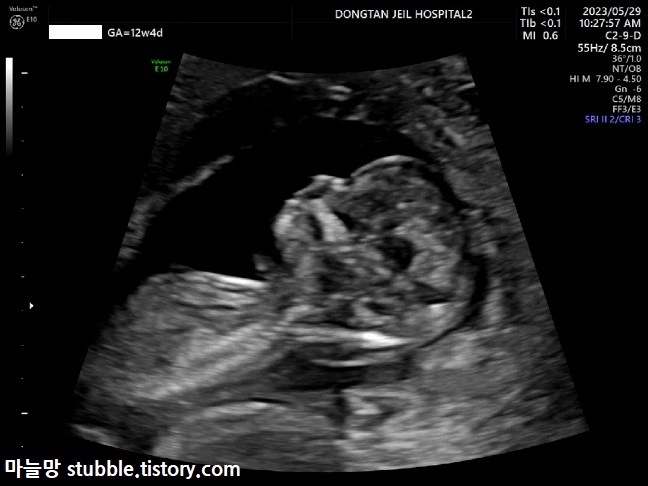

또렷해진 사람의 모습! 많이 컸지요?

이번에는 얼굴 쪽 옆모습을 잡았습니다.

얼굴이 거의 사람의 형태입니다.

다운증후군의 경우 코뼈가 안 생기는 경우도 있다고 하여 코뼈를 확인합니다.

우리 아기는 코뼈도 잘 생겨 있었어요.